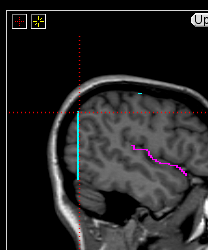

The insular cortex is “hidden” between the temporal and inferior parietal corticies. By drawing sulci lines in the sagittal view, we gain an outline of it in the coronal. Choose a sagittal slice where insula is clearly visible (Fig 1), then draw a “circle” around it (Fig 2). Do this for several slices and for both hemispheres.

Figure 1              Figure

2